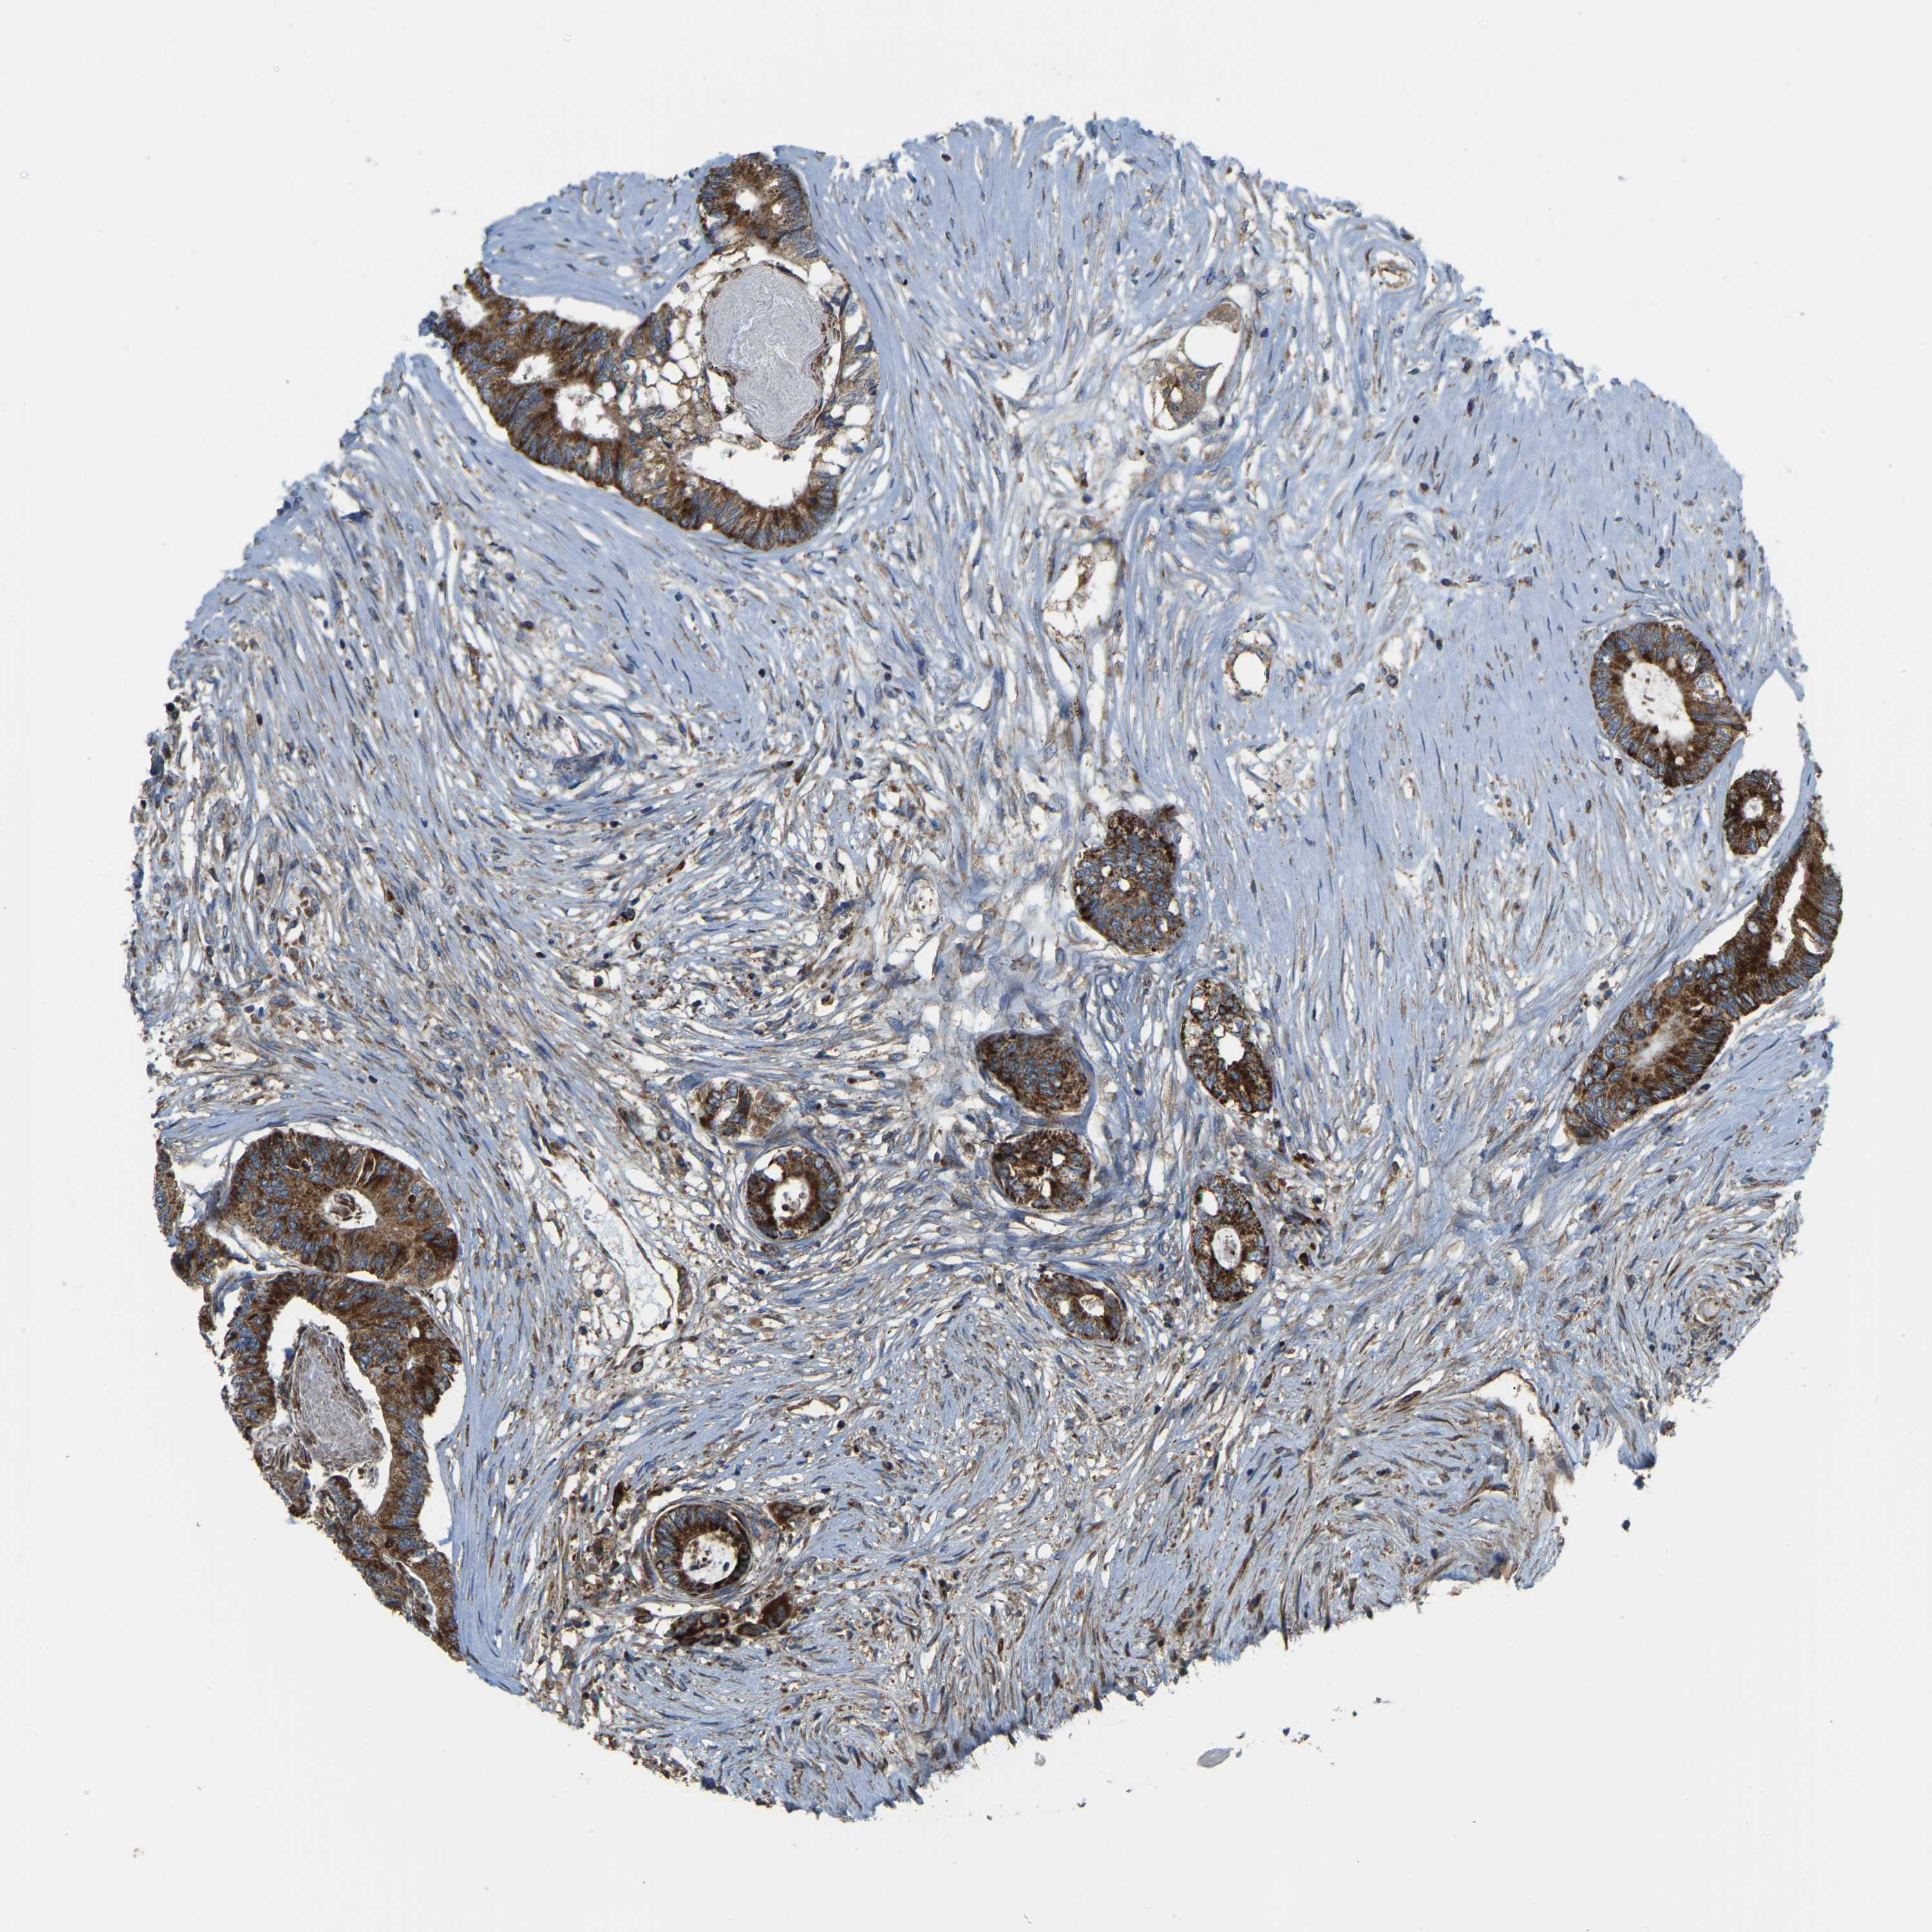

CANCER COLORECTAL CANCER Show tissue menu

Colorectal cancer

Human cancer

Colon adenocarcinoma